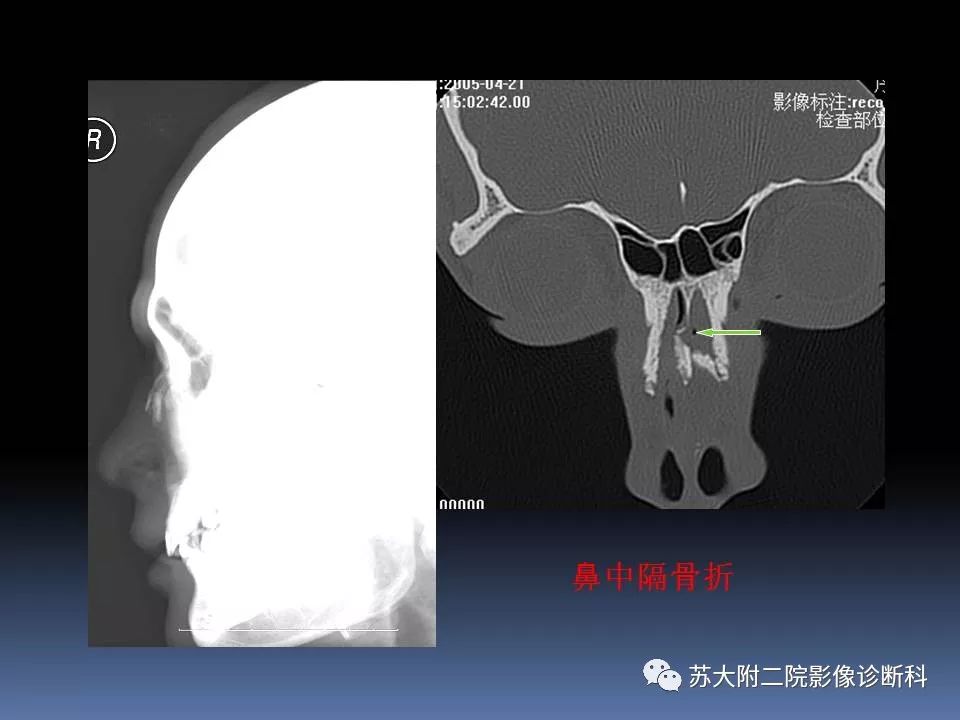

【PPT】鼻骨骨折影像诊断误区-4